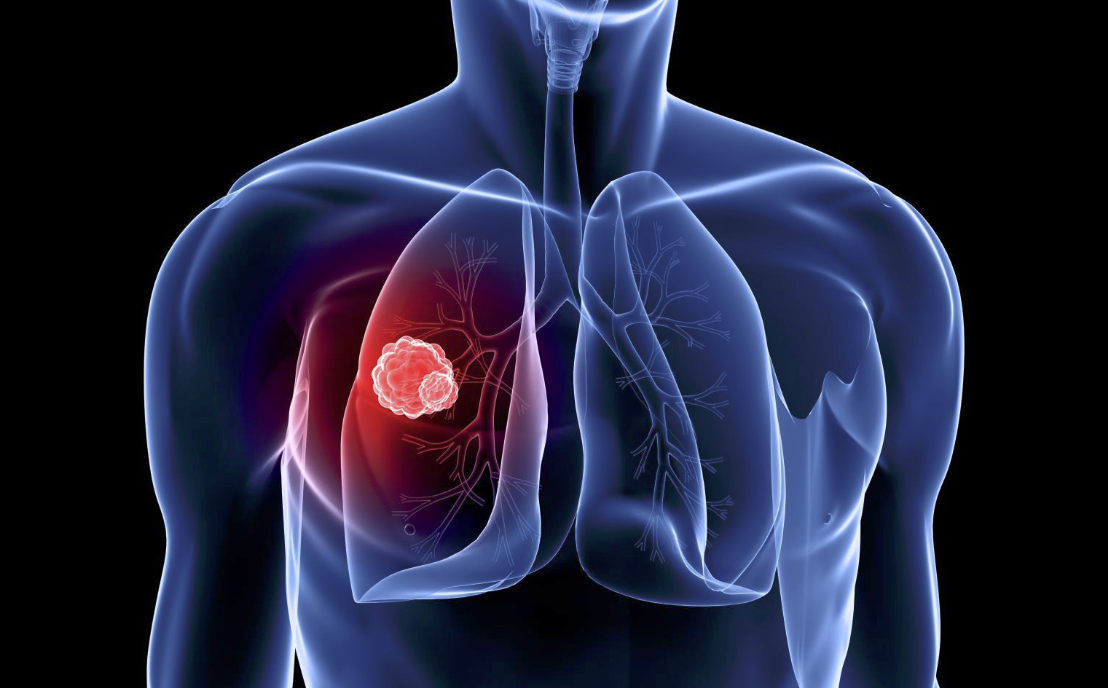

Doctors will use a number of tests — CT scan, chest X-Ray, blood work — to determine the potential severity of the disease. Essentially, cancer cells divide in the lungs in an uncontrollable manner. The growth of the said tumors compromises the ability to breathe properly. Aside from CT and PET scans, doctors also utilize lab testing and tissue sampling.

In terms of treatment, there are a few options. Depending on the severity, surgery may be looked at as the desired means of helping to ward off the disease. Cancerous tissue will literally be cut from the lung.